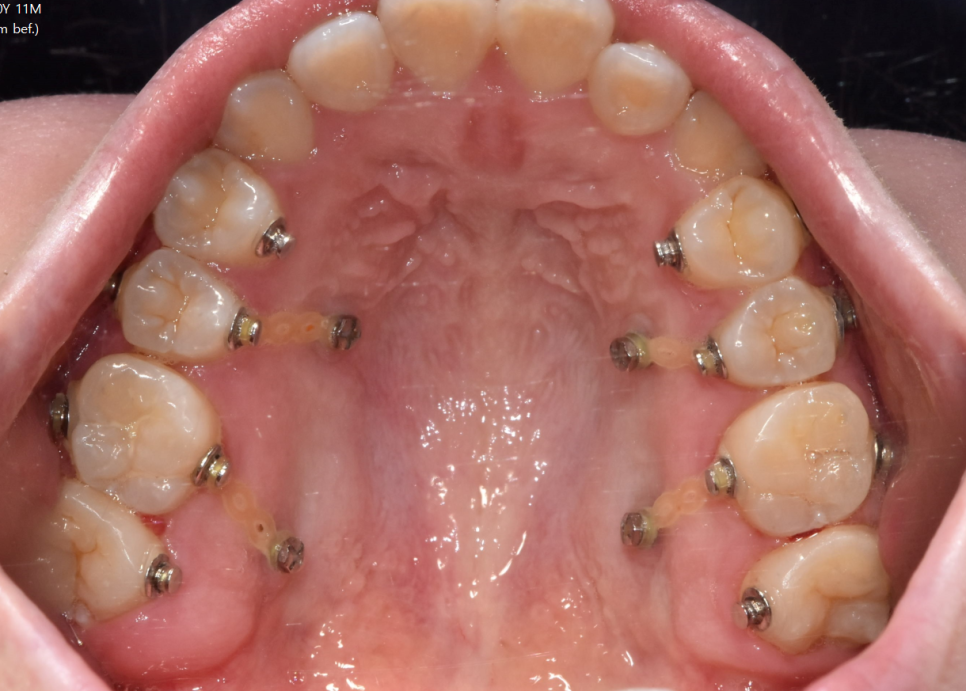

231017 입안에 장치를 달아야할 경우 양치가 어렵겠죠?

또한 입안에 장치가 많다보니 양치하는 데도

시간을 투자해야하고

먹는 음식도 조절이 필요합니다.